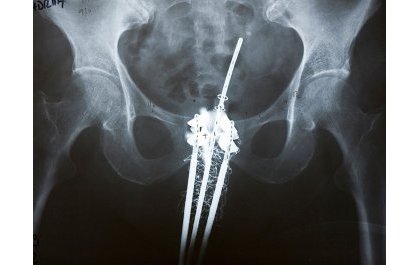

Ubwo ni uburyo bwo kuvura kanseri aho umurwayi aryama noneho imashini yabugenewe ariko iri inyuma ikohereza imirasire ahari kanseri ikayishiriza.

Ni mu gihe ‘Brachythérapie’ yo hinjizwa ‘tube’ imbere mu mubiri ahari kanseri ikagenda ikayigezaho ya mirasire neza ikayishiriza iyegereye.

Dr. Maniragaba yasobanuye ko ubwo buryo ari bwo butanga ubuvuzi bwa kanseri bwizewe cyane kurusha ‘Radiothérapie’ kuko butanga amahirwe yo kugera kuri kanseri neza.

Ati “Icyiza cy’ubu buryo ni uko bugabanya ibyago biterwa n’aho ya mirasire yanyuraga kandi bukongera amahirwe yo gukira kuko imbaraga zo gushiririza kanseri zose zijya ku rugingo iherereyeho.”